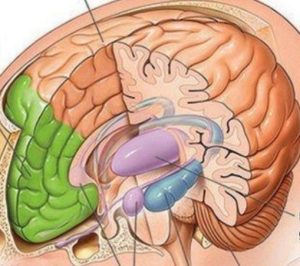

پزشک امروزی، اما تنها به مشاهدهی دو بعدی بسنده نمیکند. او در عصر تحکّم نظریهی سلولی زندگی میکند و بدن و مغز را در سه بعد میبیند. این نگاه، حاصل تحکّم نظریهی سلولی بر او و الزام به نگاه بافتی از بدن است. برای او، بدن، یک جغرافیای سه بعدی است که در آن، مشاهدهی مغز، نخاع و رشتههای عصبی، نه فقط در طول و عرض، که در عمق نیز اهمّیت مییابد. پس باید عمق اعضا نیز شکافته و کنکاش شوند. زایش مفهوم عمق، دستاورد نگاه مدرن به بدن بود. نگاهی که در آن، بیماری، عدم تعادل میان اخلاط چهارگانهی سازندهی بدن دانسته نمیشود؛ بلکه در اعماق اعضای بدن کنکاش میشود. به همین دلیل، تصویر سوم، همان تصویری است که او از مغز مطالبه میکند:

او مغز را در عمق میبیند. چرا که نظریهی سلولی به اعماق نظر میکند. او بیماری را در اخلاط چهارگانه و برهم خوردن تعادل میان آنها جستجو نمیکند. بلکه تاثیر بیماریها و آسیبها در سطح بافتی و سلولی، یکی از همان موارد تعیینکننده برای او بهشمار میرود.